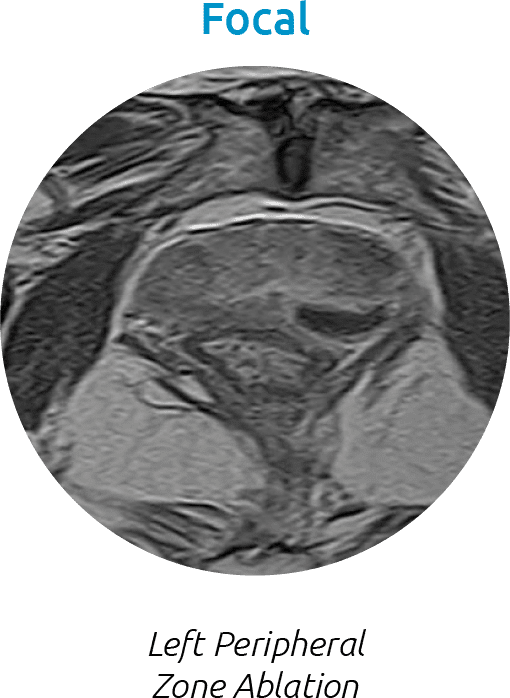

In Action: Water Vapor Ablation

Water vapor transfers energy convectively through the target prostate tissue, while respecting the natural boundaries of the prostate. Here are a few examples of water vapor ablation in different areas in the prostate.